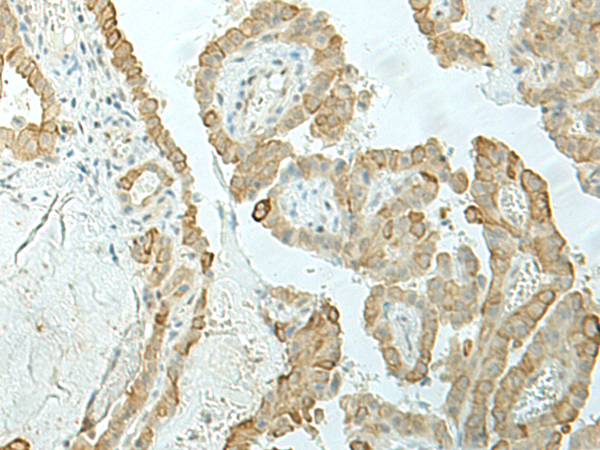

ELISA, IHC |

IHC positive control: |

Human esophagus cancer and Human thyroid cancer |

IHC Recommend dilution: |

30-150 |